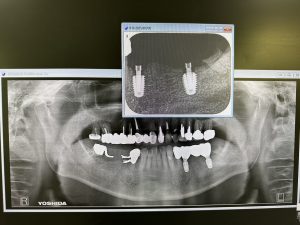

今日は2件インプラントブリッジセット

ほぼ2か月で終了

上下問わず、オペ時、計測値が良い場合は6w後再計測し著しい下降なくI SQ70以上であれば印象しています

画像からも歯肉緣からプラットフォームまでの4ミリルールが守られており良い絵面だ🤪